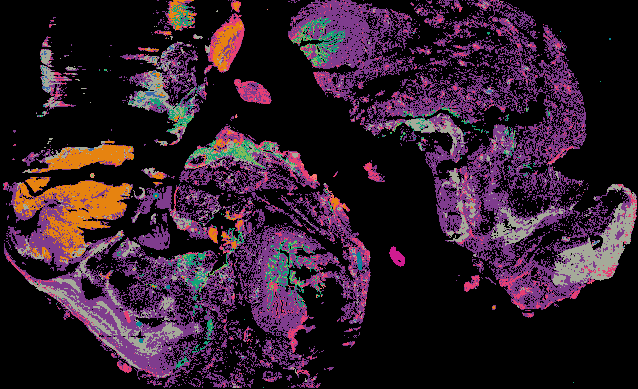

Curated stories provide access to images that have undergone a quality control step to remove failed markers, ensure appropriate channel intensity settings, and provide metadata about the underlying sample and image. Click the Minerva story icon for an interactive view of the full-resolution images.

Data image

LSP11060

LSP11064